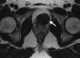

T2-hypointense prostate mass